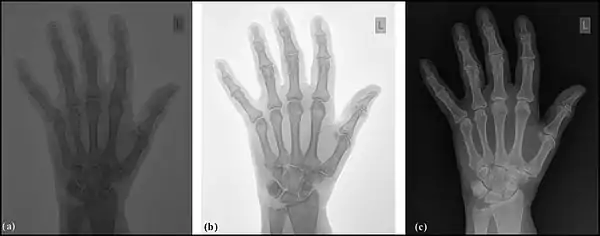

Image sampling is the process used to digitise the spatial information in an image. It is typically achieved by dividing an image into a square or rectangular array of sampling points - see the following figure. Each of the sampling points is referred to as a picture element - or pixel to use computer jargon. Although in the context of DR image receptors, the term detector element, or del, is also used. Naturally, the larger the number of pixels or dels, the closer the spatial resolution of the digitised image approximates that of the radiation pattern transmitted through the patient – see the following figure, panels (a) and (b).

Note that each pixel represents not a point in the image but rather an element of a discrete matrix. Distance along the horizontal and vertical axes is no longer continuous, but instead proceeds in discrete steps, each given by the pixel size. With larger pixels, not only is the spatial resolution poor, since there is no detail displayed within a pixel, but grey-level discontinuities also appear at the pixel boundaries (pixelation) - see panel (b) in the figure. The spatial resolution improves with smaller pixels and a perceived lack of pixelation gives the impression of a spatially continuous image to the viewer.

Image quantisation is the process used to digitise the brightness information in an image. It is typically achieved by representing the brightness of a pixel by an integer whose value is proportional to the brightness. This integer is referred to as a 'pixel value' and the range of possible pixel values which a system can handle is referred to as the grey scale. Naturally, the greater the grey scale, the closer the brightness information in the digitised image approximates that of the original image – see the following figure, panels (a) and (c). The process can be considered as the digitisation of image brightness into G shades of grey. The value of G is dependent on the binary nature of the information coding. Thus G is generally an integer power of 2, i.e. G=2m, where m is an integer which specifies the number of bits required for storage. Examples of values of G are 1,024 (m=10) in fluoroscopy, 2,048 (m=11) in angiography and 4,096 (m=12) in digital radiography. Note that the slight difference between the brightness in an analogue image and its pixel value in the digital image is referred to as the quantisation error, and is lower at larger values of G.